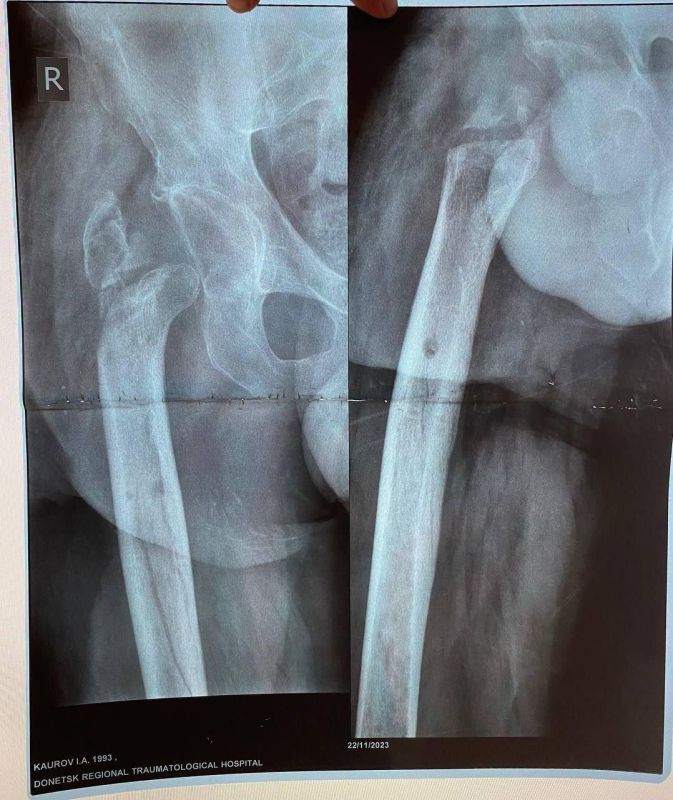

Об этом сообщила министр здравоохранения ЛНР Наталия Пащенко.Руководитель Минздрава рассказала, что борьба сержанта из ЛНР, мужчины 1993 года рождения, длилась три с половиной года. За это время он проходил лечение в десяти госпиталях, в том числе в...

Уникальная операция в Луганской республиканской клинической больнице вернула ветерану специальной военной операции (СВО) возможность ходить без хромоты. Об этом сообщила министр здравоохранения ЛНР Наталия Пащенко. Руководитель Минздрава...

Об этом сообщила министр здравоохранения ЛНР Наталия Пащенко в своем телеграм-канале.Боец ушел на фронт 25 февраля 2022 года, прошел через горнило Херсонщины, а тяжелое ранение получил 28 августа.«Из-за обширных повреждений и многократных операций...